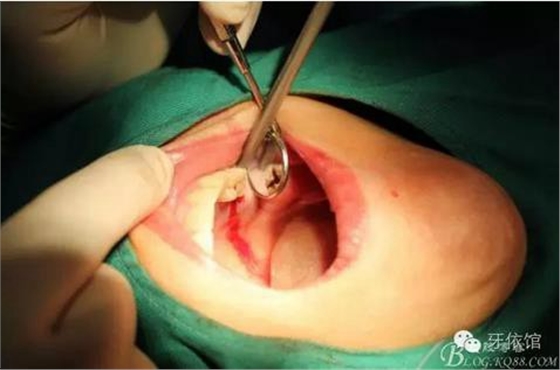

依次拔除3個根

先在右上7的位置擴孔同時做內(nèi)提升